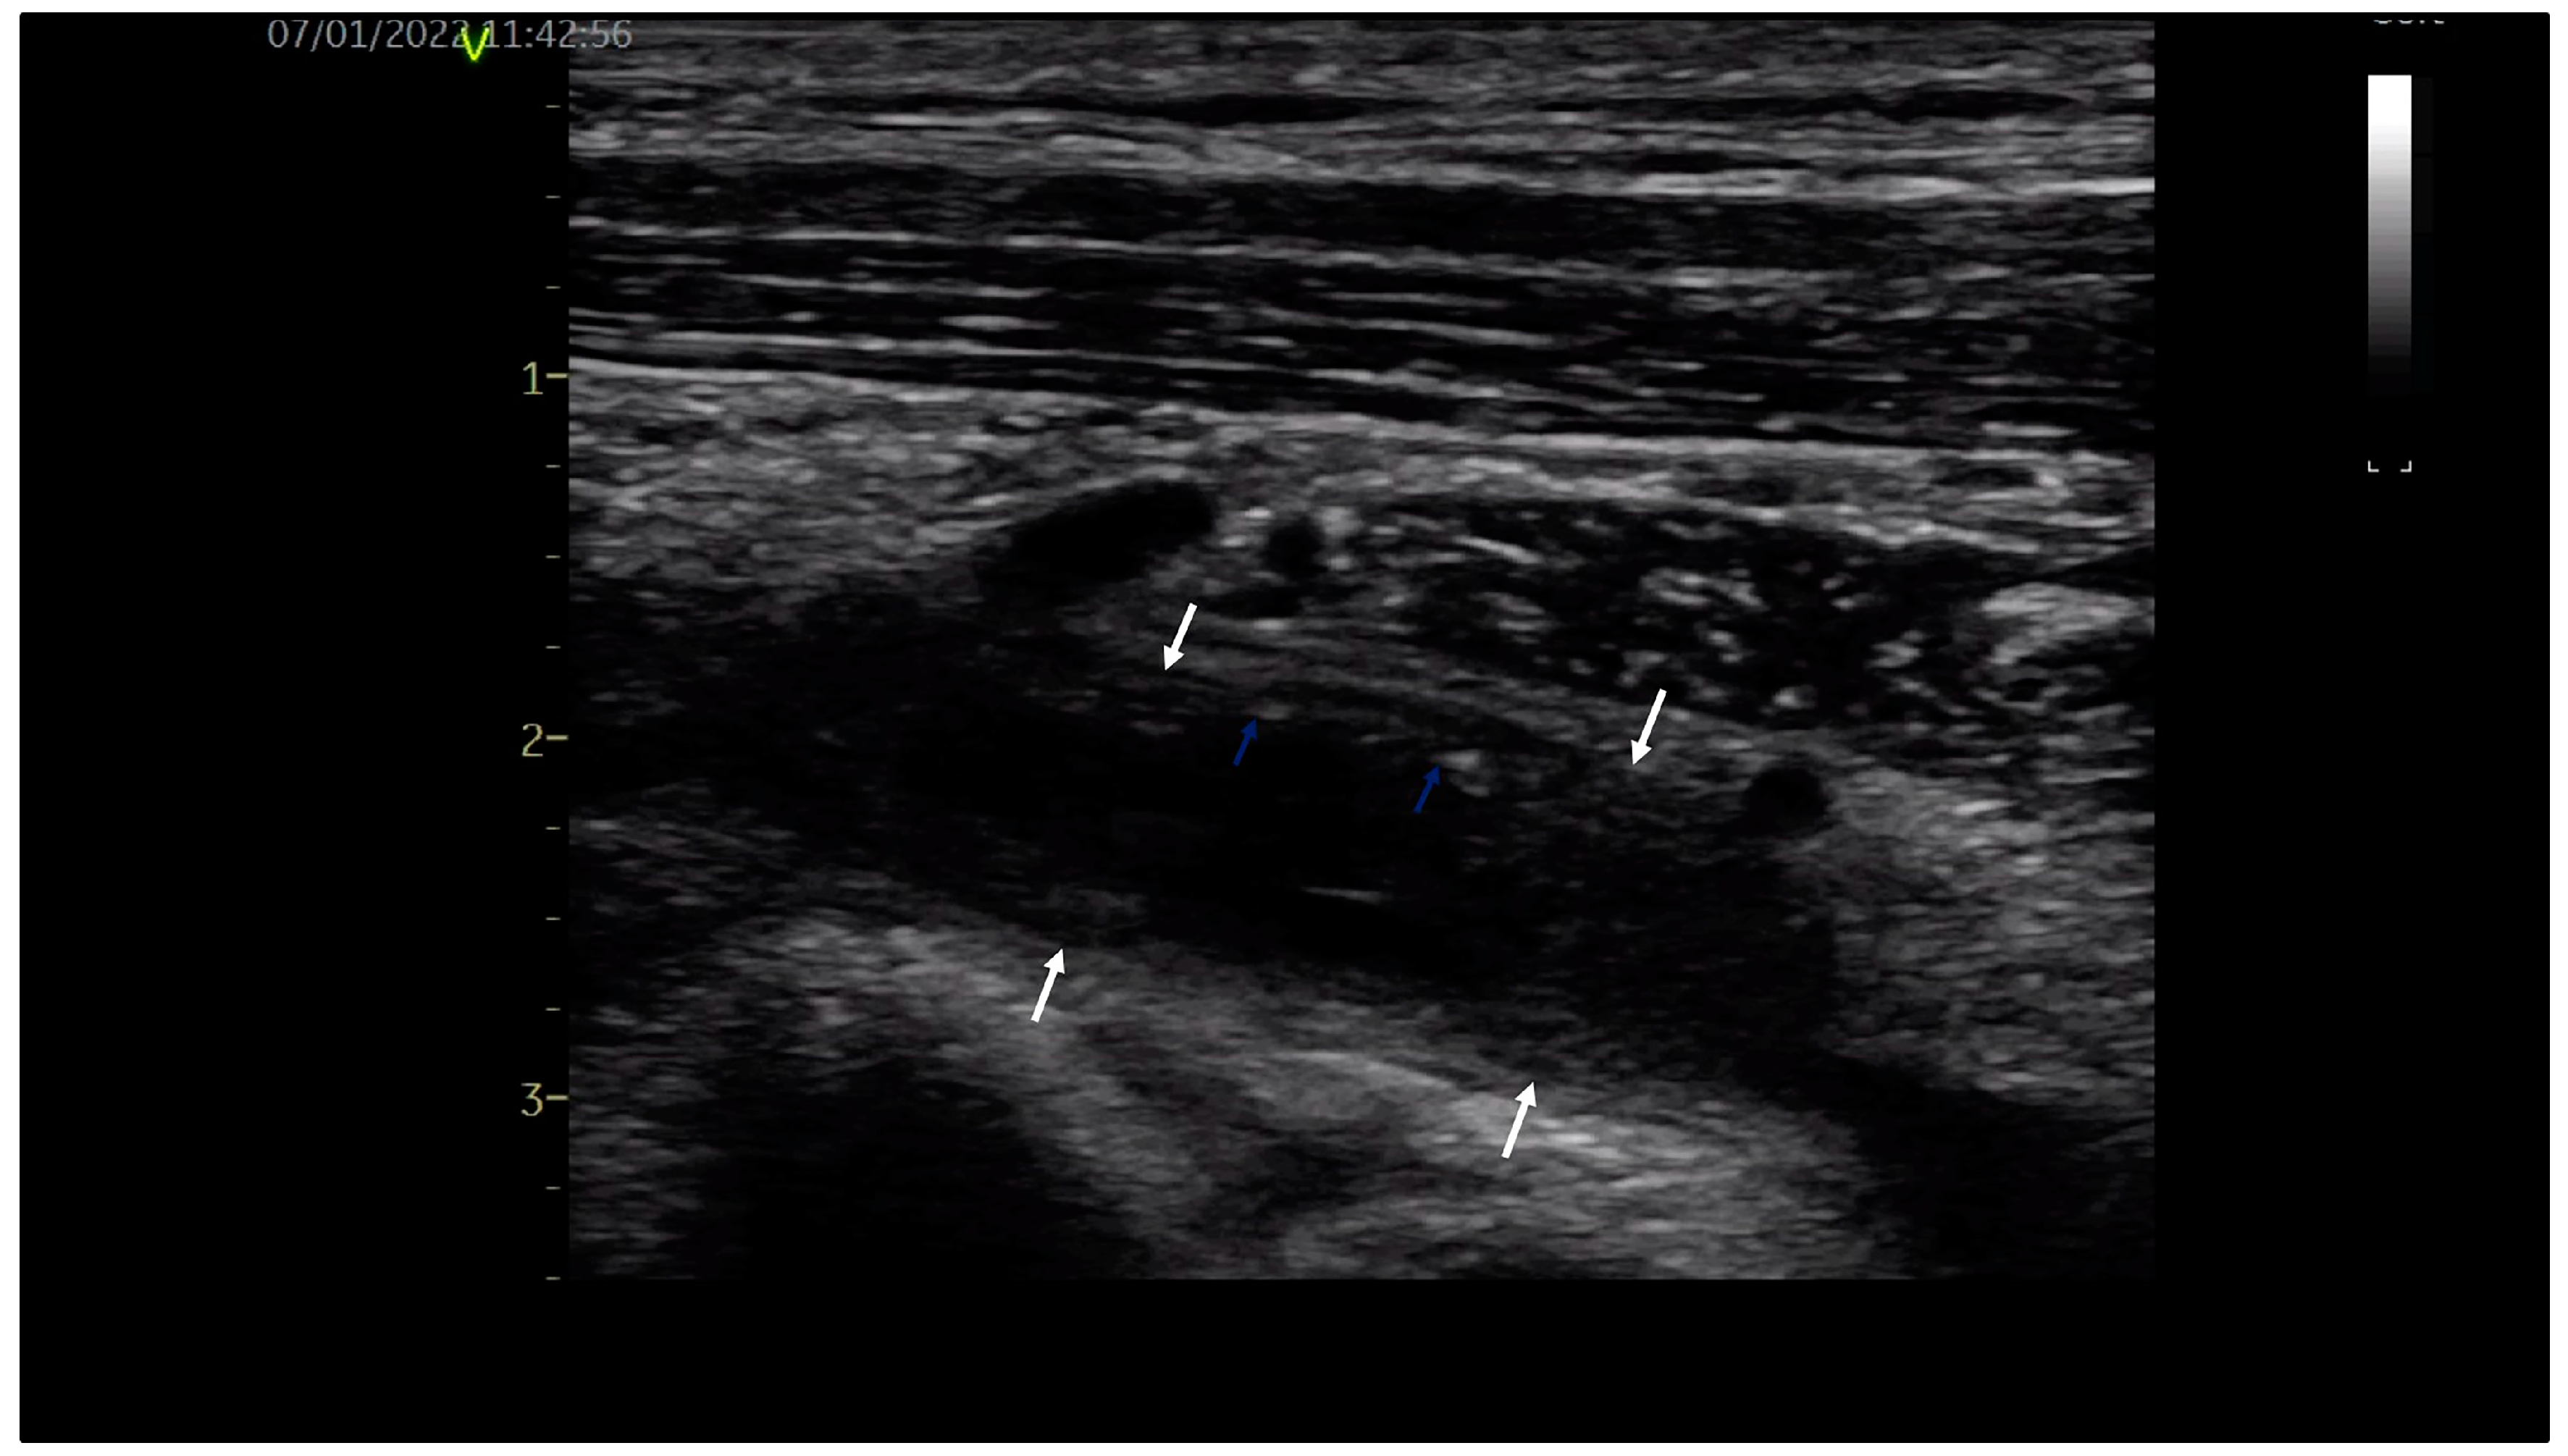

A 32-year-old young orchestra conductor, a healthy male, was admitted to our department with pain in the neck, left shoulder and arm associated with arm swelling, cyanosis and dilated collateral veins over the proximal upper limb and upper chest. The high clinical suspicion of upper limb DVT was confirmed by venous duplex ultrasound, revealing occlusive thrombus in the left subclavian and axillary veins with extension into brachial veins, as shown in Figure 1. Exclusion of thrombophilia and occult malignancy supported the final diagnosis of primary, effort-related, subacute (beyond two weeks) left DVT of the axilosubclavian and brachial veins, the venous form of TOS. Due to the late diagnosis of vTOS, oral anticoagulation with a direct oral anticoagulant (DOAC), Apixaban 5 mg bid, was initiated.

When there is a high clinical suspicion of upper extremity DVT, diagnosis is confirmed with venous ultrasound, showing dilated veins, partially compressible or incompressible thrombotic material and absence of venous flow in cases of obstructive thrombus. It is non-invasive, inexpensive and has a sensitivity of 97% and a specificity of 96% [3]. CT and MRI are ccomplementary investigations, more likely used for a better evaluation of local anatomy. The patient was not sent for venous ultrasound until later in our department, when the clinical picture was highly suggestive for upper extremity DVT.

Figure 1. Venous ultrasound: subacute left subclavian vein thrombosis with hypoechoic thrombotic material (white arrows) and small hyperechoic areas (blue arrows).